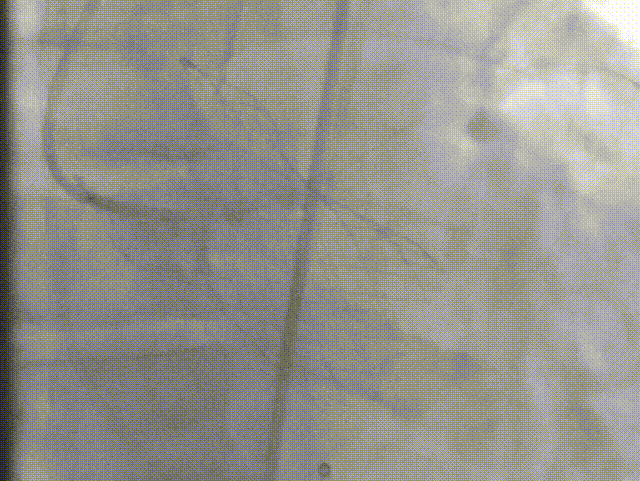

术者采用患者右侧主入路,顺利完成导丝和猪尾跨瓣等准备工作。进Landerquist超硬导丝,采用25mm球囊进行预扩,仔细评估冠脉风险后,决定对冠脉采取保护措施。根据球囊扩张情况,术中决定使用金仕生物的ProStyle预装干瓣TAV32。打开包装后,很迅速的完成了瓣膜和系统植入前的准备。输送过程系统和瓣膜轻松过弓并顺利跨瓣;开始初步释放,然后快速起搏下释放,发现位置略高后进行回收,重新定位后最终成功完成释放。反复造影发现冠脉存在阻塞风险,武汉协和团队按照风险预案在左冠植入4.0*18mm支架进行保护。术后显示左右冠脉血液灌注通畅,术后超声测量峰值流速1.45m/s,峰值压差8mmHg,几乎无瓣周漏。入路闭合顺利,无心脏及血管并发症,手术成功。

术后评估